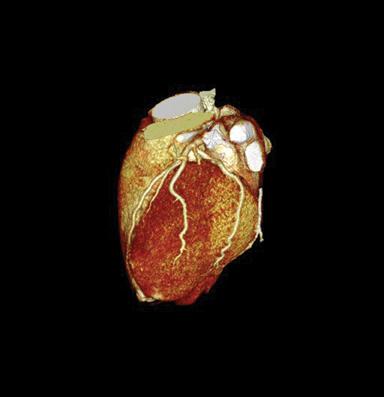

This image from an iCT scanner was done to evaluate coronary artery disease. The scan parameters were: 100 kVp, 50 mAs, CTDI vol 6.3 mGy, DLP 68.3 mGy x cm, iDose4 level = 3, effective dose 0.9 mSv. More images are below.

Because iDose4 significantly improves spatial resolution and preserves the “natural” appearance of images, image quality improvements are achieved.

“We experimented with low-dose/low-energy scans in the past with suboptimal image quality. Therefore, the dose vs. image quality was not beneficial,” Dean Blair RT(R)(CT), supervisor of the CT department at SOMC said. “Then we installed the iCT with iDose4. Now, our results show an increase in image quality at low dose.”

In addition to the low-energy, low-dose benefits SOMC has experienced, Blair also noted that SOMC has been able to use low injected contrast imaging as a result of the fast scan times and rotation speeds of the iCT.